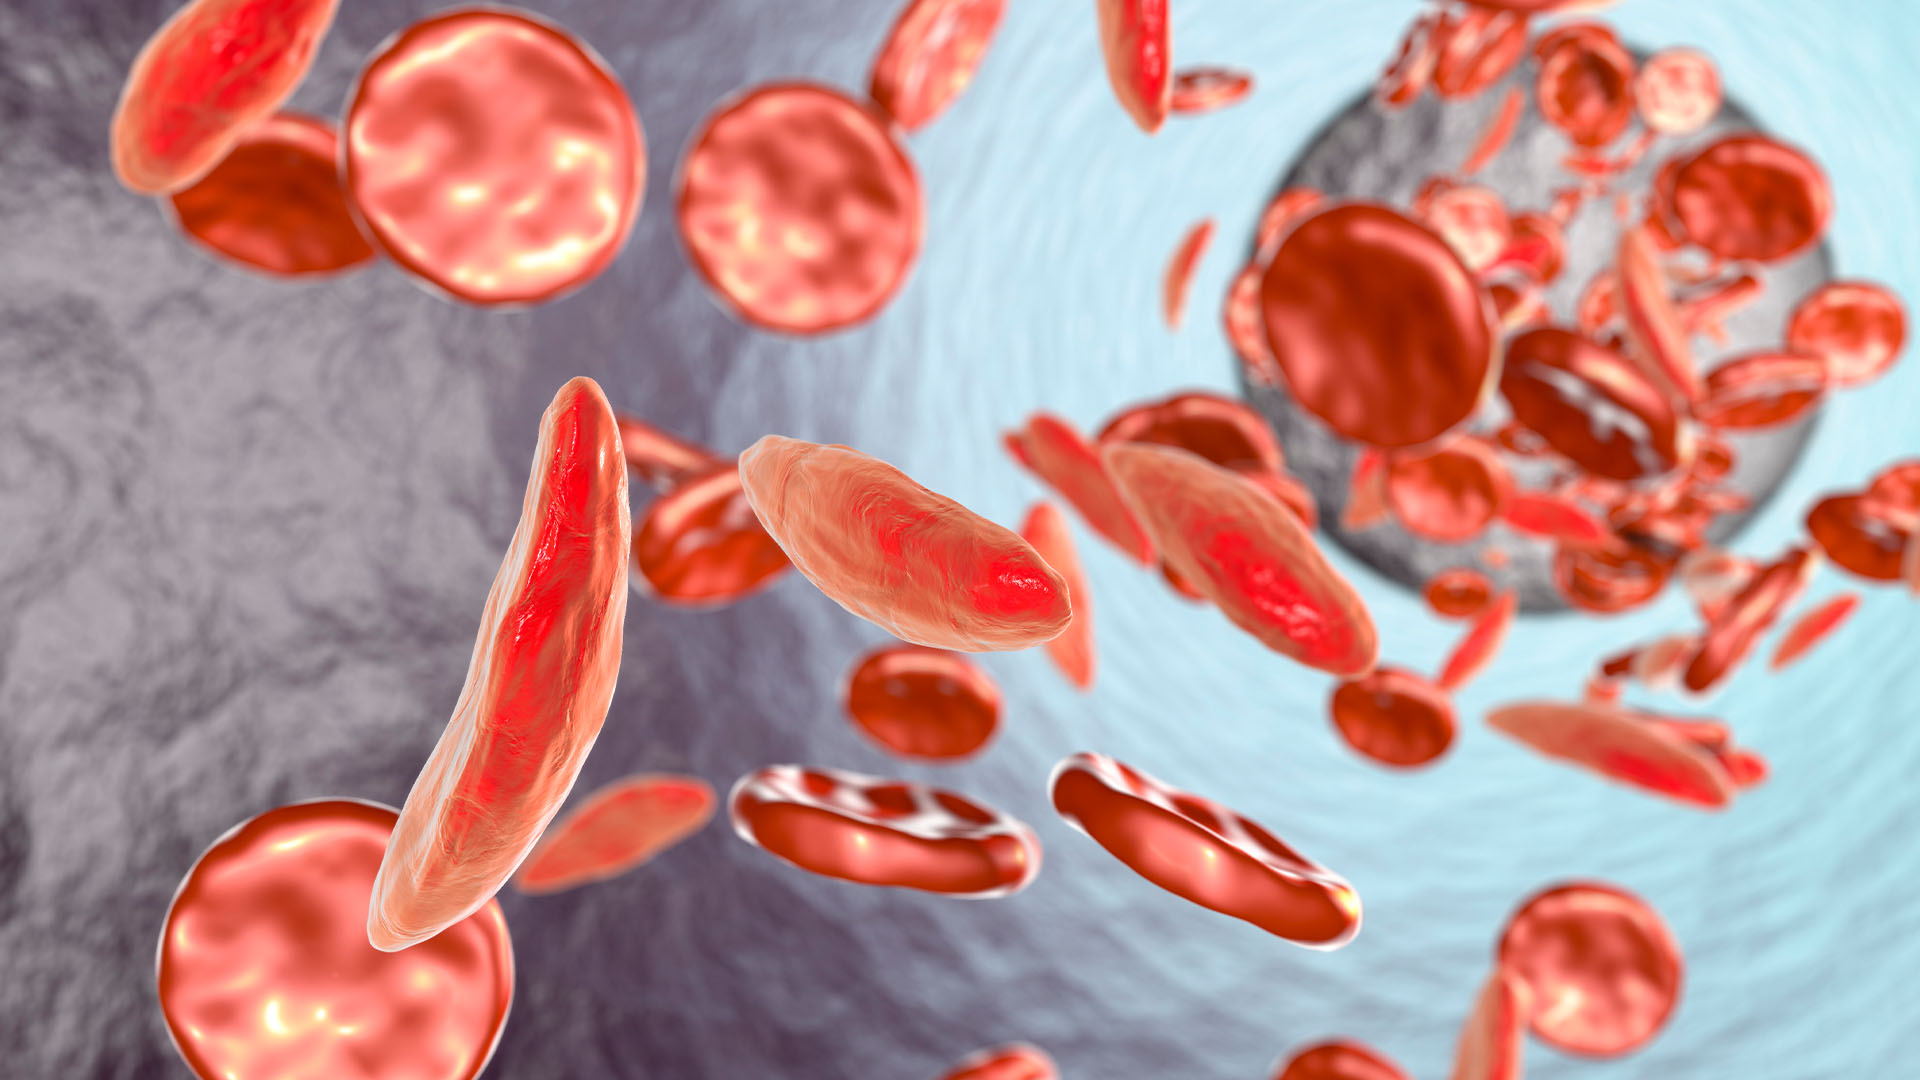

The bacteria, called Carnobacterium pleistocenium, might also be interesting to medical researchers.

"The enzymes and proteins it possesses, which give it the ability to spring to life after such long periods of dormancy, might hold the key to long-term, cryogenic -- or very low temperature -- storage of living cells, tissues and perhaps even complex life forms," Hoover said.